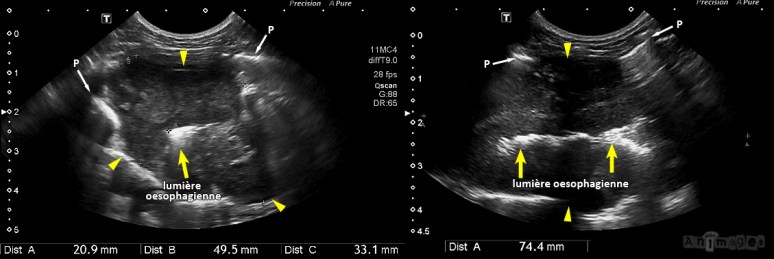

Une large masse (têtes de flèches) hétérogène et globalement hypoéchogène infiltrait de façon circonférentielle la paroi de l’œsophage, formant une masse fusiforme de 5 cm d’épaisseur sur plus de 7.4 cm de longueur. Les extensions crâniale et caudale de la masse ne pouvaient toutefois être évaluées en raison de la superposition des poumons. L’épaississement pariétal (jusqu’à 21 mm) était associé à une perte de la démarcation des couches. L’accès aux nœuds lymphatiques était aussi été limité par la présence d’air pulmonaire (P). Cet épaississement circonférentiel marqué de la portion moyenne de l’œsophage thoracique montrait donc des caractéristiques échographiques compatibles avec une infiltration néoplasique (lymphome, carcinome, mastocytome, sarcome histiocytaire, sarcome musculaire), bien qu’une œsophagite granulomateuse n’était pas complètement écartée (les flèches jaunes pointent vers la lumière oesophagienne).